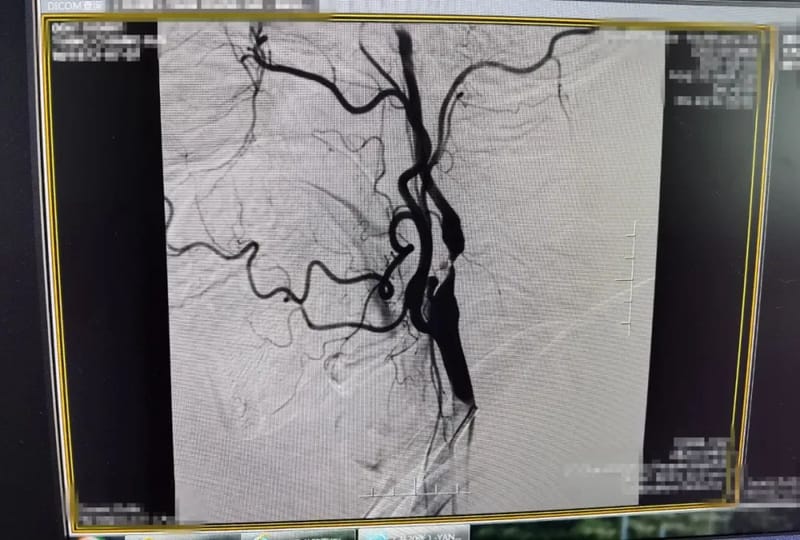

术前造影颈内动脉严重狭窄